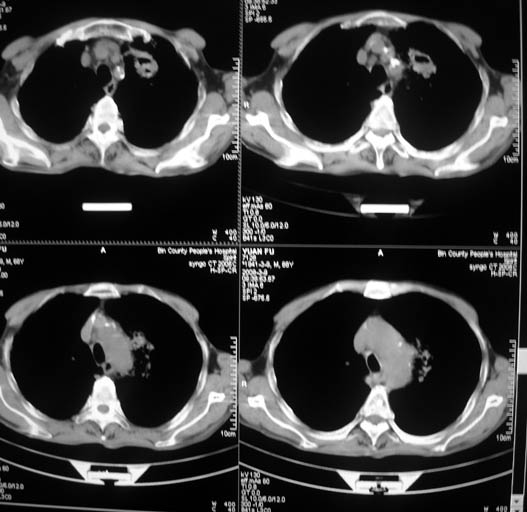

标题: CT18577:男,68岁,左肺占位。 [打印本页]

标题: CT18577:男,68岁,左肺占位。

男,68岁,左上肺占位,肺门淋巴结转移?

支持楼主,最好能有强化资料

1)考虑左肺上叶尖段周围型肺癌并阻塞性肺炎,纵隔淋巴结转移。2)心包少量积液。

1)考虑左肺上叶尖段周围型肺癌并阻塞性肺炎,纵隔淋巴结转移。2)心包少量积液

1)考虑左肺上叶尖段周围型肺癌并阻塞性肺炎,纵隔淋巴结转移。

2)心包少量积液。